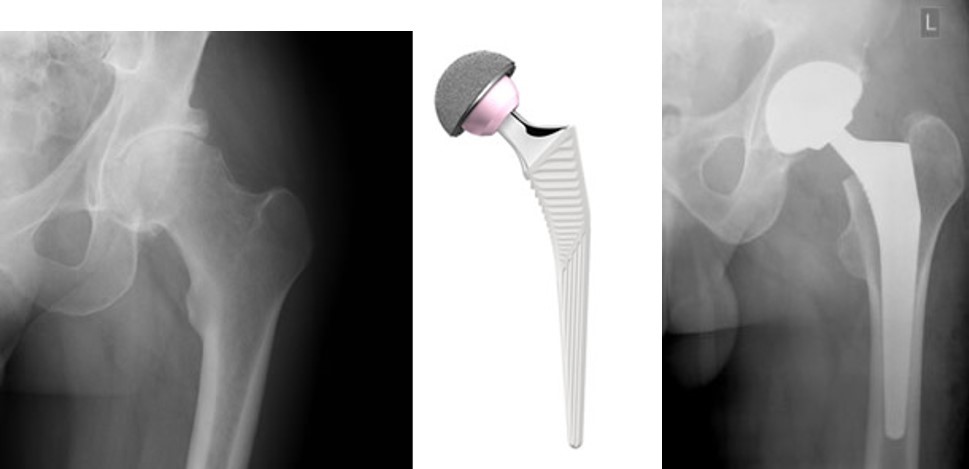

Hip X-Rays and Prosthetic Hip Joint

X-rays showing before and after hip replacement surgery, with the type of prosthetic (artificial) hip joint used in the middle.